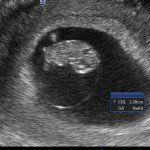

Con l’ecografia transvaginale è possibile vedere dopo circa 3 settimane dal concepimento la camera gestazionale nella cavità uterina. Successivamente è possibile visualizzare l’embrione (3-5 mm.) a circa 6 settimane dall’ultima mestruazione (4 settimane dal concepimento) ed a questo periodo è già visibile l’attività cardiaca fetale Anche i primi dettagli sulla morfologia fetale (polo cefalico, abbozzi degli arti) sono visualizzabili più precocemente con l’ecografia transvaginale, risultando essi visibili intorno a 8-9 settimane.